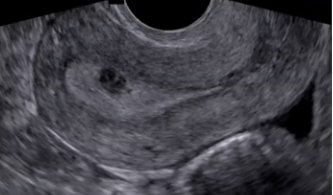

A partir dos dados clínicos e identificação de massa palpável ao exame físico, suspeitamos da doença, porém os exames de imagens são essenciais para o diagnostico e definição de tratamento.

Através da Ultrassonografia e Ressonância magnética de pelve é possível identificar e classificar os miomas, permitindo o planejamento do tratamento adequado.

A histeroscopia diagnostica tem o papel tanto de diagnosticar como de melhor classificar os miomas submucosos para programação da retirada dos miomas por histeroscopia cirúrgica.